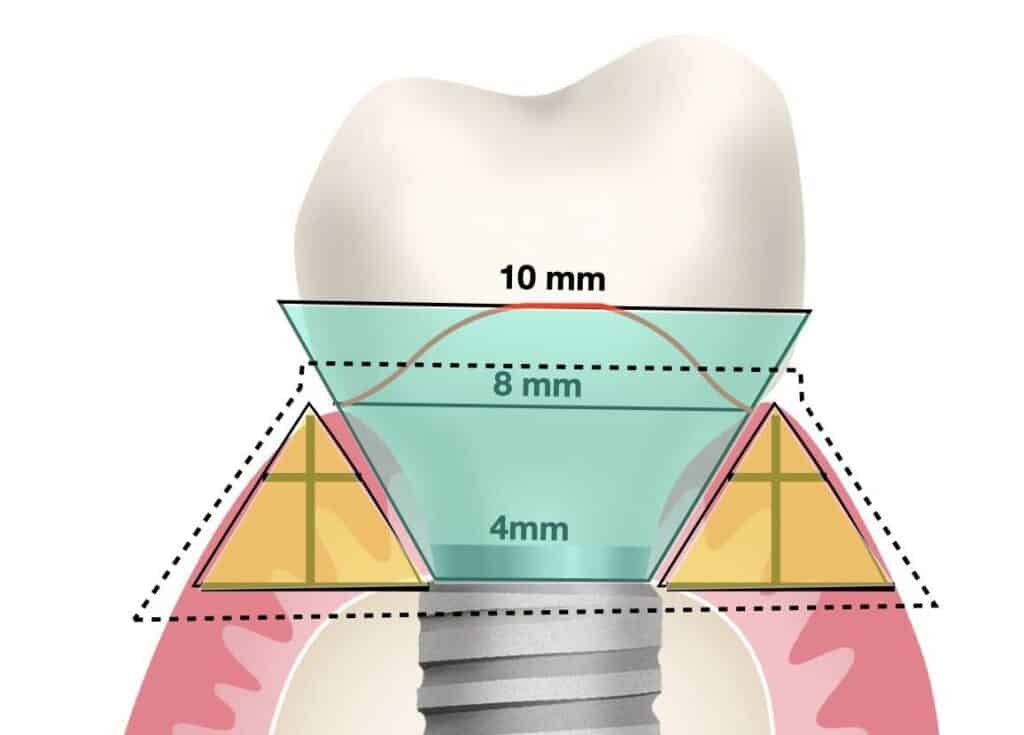

A consistent finding in peri-implant mucosa dimensions was that the mucosal width at the implant platform was always more than the corresponding mucosa height. So in simple terms, if you draw a line at the level of osseointegration from the implant shoulder to the outside margin of the mucosa, this will always be more than the corresponding height of the soft tissue. In posterior sites the width will exceed the height by a factor of 1.5 to 2. Interestingly, this is the opposite in physiological periodontium, where the periodontal tissue around natural teeth are typically more high than wide. Now in the case of tissue level implants, the corresponding width is to be counted at the interface of the rough surface. Whether tissue or bone level implants, the vertical soft tissue architecture is being established on top of the marginal bone.

So first thing to look for when trying to build the pyramid is a vast piece of flat land to set the base. Yes, we do need a certain minimum height of soft issue to establish a healthy and sustainable peri-implant tissue anatomy and the larger the flat base the higher you will be able to reach with your pyramid. But what is the best way to secure the flat land to build on?

As we discussed ,the pyramid will be build just next to our implant, thus the “flat land” we are looking for is primarily the circumferential bone around the implant. For example, considering that the most challenging aspect of the peri-implant mucosa dimensions in the aesthetic zone is typically in the buccal area, placing the implant in the palatal part of the prosthetic comfort zone can ensure more space for the “pyramid” base, even in the presence of thinner mucosa. This is also why a bone augmentation with GBR in the same location is in most cases enough to secure adequate soft tissue thickness as well, by establishing the essential base to support the pyramid. Sometimes the implant position might be slightly to the palatal side of the prosthetic comfort zone at the expense of the palatal tissue space, but in most cases the angle of the palatal bone results in supporting a wider pyramid of the palatal mucosa, with no impact in the aesthetics, which is thus less susceptible to problems.

Observe the dimensions of the buccal peri-implant mucosa 18 months after implant placement with Guided Bone Regeneration of a self contained buccal bone defect. The overall mucosa before surgery was actually only 1.3 mm thick, but thanks to the augmentation of the bone, there is sufficient "flat land" to establish a wide base of the pyramid (5.1 mm) and the essential soft tissue height (3.5 mm).It's not a townhouse, it's a pyramid, but will do the job!

And last but not least, the design of the prosthesis of course: The Emergence Profile, the Transmucosal part of the abutment and the prosthesis. Remember, this is the reason that peri-implant tissue exists. This is the concrete wall we built next to the tree. That might explain how altering the shape of the Emergence profile from Concave to convex can predictably cause mucosal recession, an observation that we can use to our advantage or ignore to our detriment..! In essence, implant, prosthesis and mucosa are all parts of the same interrelated system, sharing the same space: enlarging one side, reduces the other!